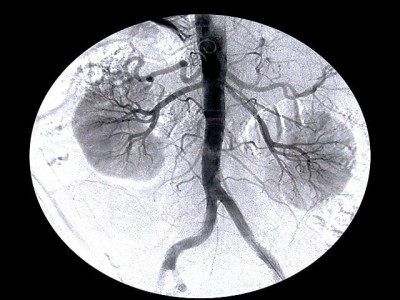

Kidney Stones

Nawaz advised surgery for removal of kidney stones

Pulverising kidney stones in Rawalpindi through non-invasive procedure

Doctors at BBH introduce new lithotripters to treat disease for free